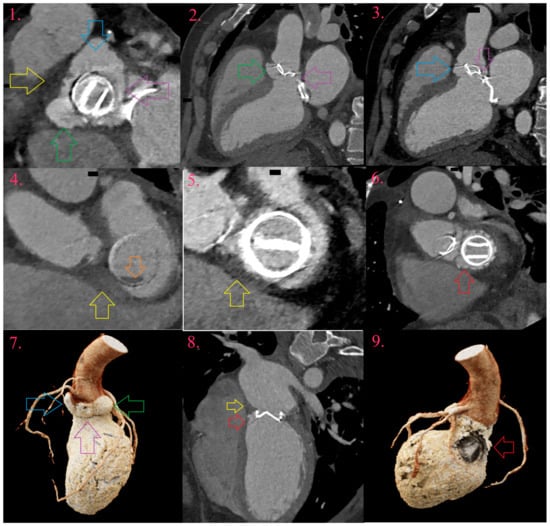

9.1. Mitral Valve Infective Endocarditis

9.2. Aortic Valve Infective Endocarditis